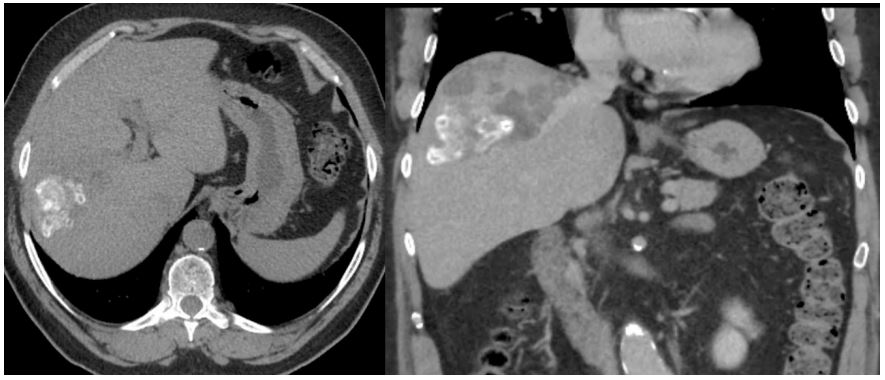

His medical history included ischemic heart disease, arterial hypertension, auricular fibrillation, and sleep apnea syndrome. He presented with alveolar echinococcosis with a liver lesion 67×70 mm in diameter with central calcifications, hypermetabolic at PET tomography, heterogeneous aspect, cystic component, perilesional vascularization, and positive anti-Ecchinoccus antibodies (Figure 1). He was initially treated with 400 mg of albendazole twice daily and then underwent liver surgery. Extension of the lesions indicated a right hepatectomy extending to segment 4b using the laparoscopic approach. There was an important fibroinflammatory infiltration around the hepatic lesion, and extensive adhesiolysis was necessary to cleave the lesion from the diaphragm and remove some muscular fibers. However, no diaphragmatic damage was observed at the end of the surgery. Histology confirmed alveolar echinococcosis lesions in the resected liver invading the diaphragmatic muscle fibers.

Figure 1: Initial liver lesion with central calcifications: alveolar echinococcosis.